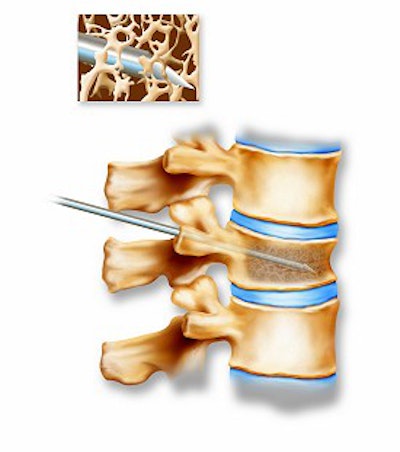

A vertebral compression fracture causing pain and spinal deformity (above). Below, a biopsy needle is guided into the fractured vertebra through a small incision in the skin. Inset shows a magnified view of the interior of the osteoporotic vertebra with the needle in place.